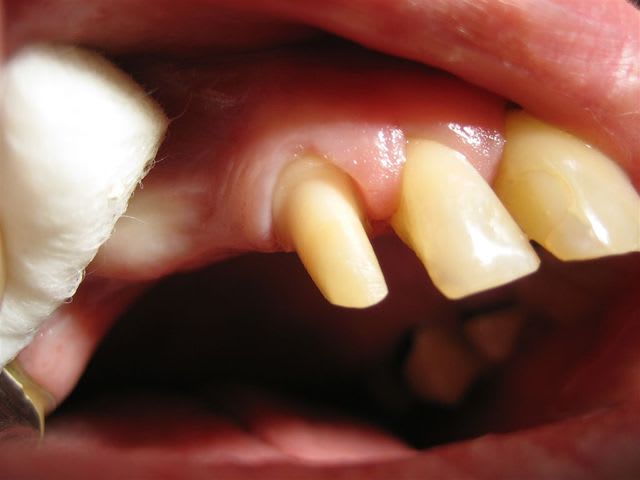

... un autre cas, mais ça ressemble toujours à ça >

... joli, très joli!

Il m'arrive aussi parfois de délaisser le bandeau métallique palatin au profit de la petite tige en disto-palatin ... je devrais le faire plus souvent.

Il y a longtemps j'ai essayé un autre type de limite; congé large en V,M,D (pour la masse d'épaulement) et congé étroit en DP, P, MP avec un chanfrein (biseau pour le métal) venant rejoindre le congé large ... assez compliqué à réussir en bouche.